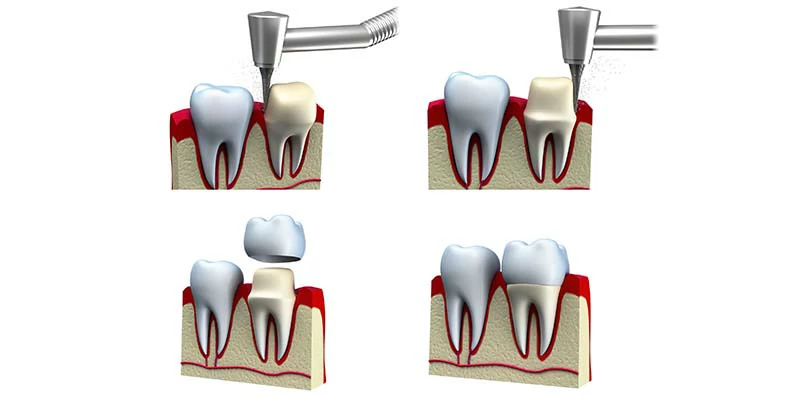

هو عبارة عن غطاء يُوضع فوق السن ليأخذ شكله؛ من أجل الحفاظ على ما تبقى من السن، ولاستعادة وظيفة السن الرئيسية، والمظهر الطبيعي للأسنان، ولتقوية الأسنان الضعيفة والمتحللة.

قبل تثبيت التاج في مكانة، يحتاج الطبيب إلى إزالة جزء صغير من مينا السن الأصلي الذي سوف يتم تركيب الطربوش عليه؛ حتى يضمن ثبات التاج.

تُصنع هذه التيجان أو الطرابيش من مواد خاصة، مثل المعادن والراتنج وبعض أنواع الخزف، ولها العديد من الاستخدامات الأخرى، كـ أنها تحمي وتدعم الأسنان المتشققة، ويمكن استخدامها لتغطية الأسنان المتغير لونها، كما تُستخدم في تغطية الأسنان المعالجة بقناة الجذر.